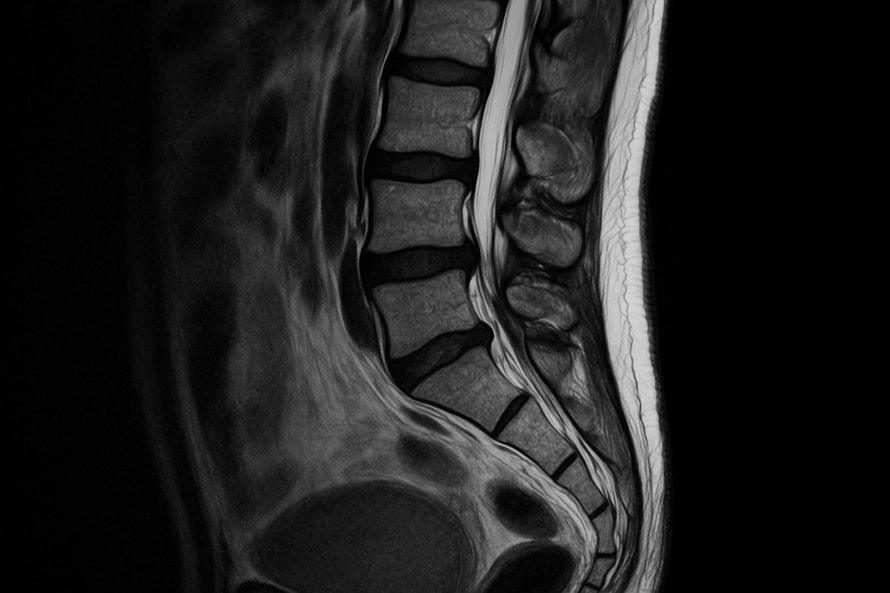

Магнитно-резонансная томография крестцово-копчикового отдела позвоночника — информативный способ визуализации, позволяющий изучить мягкие ткани, нервные окончания и костные структуры в области нижнего отдела спины. Благодаря высокой точности снимков врачи могут выявить патологии, которые не определяются другими методами. Исследование эффективно при нарушениях чувствительности, болях и дискомфорте в области таза, а также при хронических заболеваниях.

Метод основан на эффекте ядерного магнитного резонанса. Это позволяет получить послойные изображения отдела позвоночника без облучения. Особенно актуально сканирование при заболеваниях позвоночника, связанных с защемлением нервов, воспалением или подозрением на новообразования. В отличие от рентгенографии или КТ, томография позволяет изучить даже мелкие сосуды, нервные сплетения и мышечные волокна, расположенные в труднодоступных зонах. При необходимости исследование дополняется контрастным усилением для более четкой дифференциации тканей.